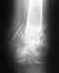

Следует обратить внимание на рентгенограммы таза, которые не представлены. Уместно сделать и компьтерную томографию.

О том и речь, что поскольку таз - кольцо, при наличии перелома в передней части вероятно повреждение таза и в задних отделах.